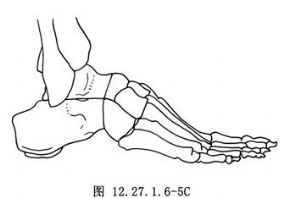

用大切骨刀切除跟骨和距骨关节面,根据畸形的性质与程度,切除适量的楔形骨质。如为内翻畸形,应切除以外侧为基底的楔形骨质;反之如为外翻畸形,则应切除以内侧为基底的楔形骨质(图12.27.1.6-5A)。用切骨刀横行切除跟骰关节面,如有足前部内收,应切除以外侧为基底的楔形骨质;如为外展畸形,则应切除以内侧为基底的楔形骨质(图12.27.1.6-5B)。切除距舟关节面,如有高足弓,应切除以背侧为基底的楔形骨质。如显露困难,宜在内侧做一纵行辅助切口。切骨后观察足部畸形矫正情况,适当修整骨面,使三处骨面有良好接触,以便完全矫正畸形,并有利于骨愈合(图12.27.1.6-5C)。保留取下的骨质,去除软骨部分,作为松质骨植骨,植于各关节周围,要特别注意在距舟关节部位多植些碎骨,防止形成假关节。